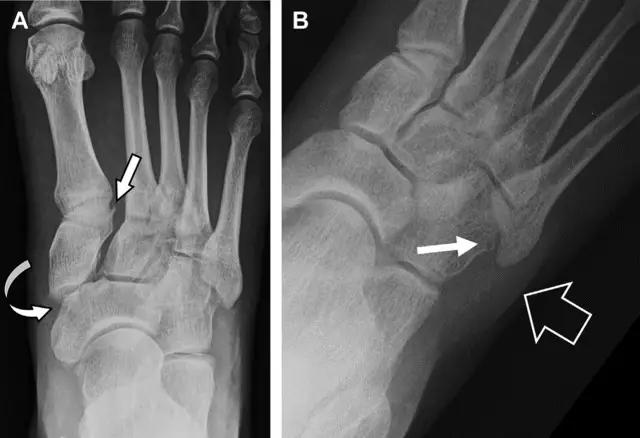

11 Segond 骨折

Segond 骨折是发生在胫骨平台外侧的垂直撕脱性骨折(图 4)。这种骨折在前后位 X 线片上显示最佳。

屈曲位时膝关节受到内旋*力暴**作用,导致皮质骨撕脱性骨折,这种骨折常发生在运动员身上。常引起股骨内髁和胫骨平台后内侧骨挫伤,75%~100% 的患者伴前交叉韧带断裂,33% 的患者伴外侧半月板损伤。

图 4 一位足球运动员的 Segond 骨折

A 正位片示关节线下方胫骨外侧皮质撕脱(箭头)。B MRI 冠状位 T1 加权像示附着于髂胫带的骨折碎片(空箭头)。

12 反向 Segond 骨折

胫骨平台内侧皮质骨撕脱性骨折,被称为内侧 Segond 骨折或反向 Segond 骨折(图 5)。这种骨折的旋转机制与 Segond 骨折相反,该骨折与后交叉韧带断裂及内侧半月板损伤相关。

图 5 一位足球运动员的反向 Segond 骨折

A 正位片示关节线处的胫骨内侧见一细小骨折片(箭头)。B MRI 冠状位 T1 加权像示骨折片出现在内侧副韧带关节囊附着处(方框)。